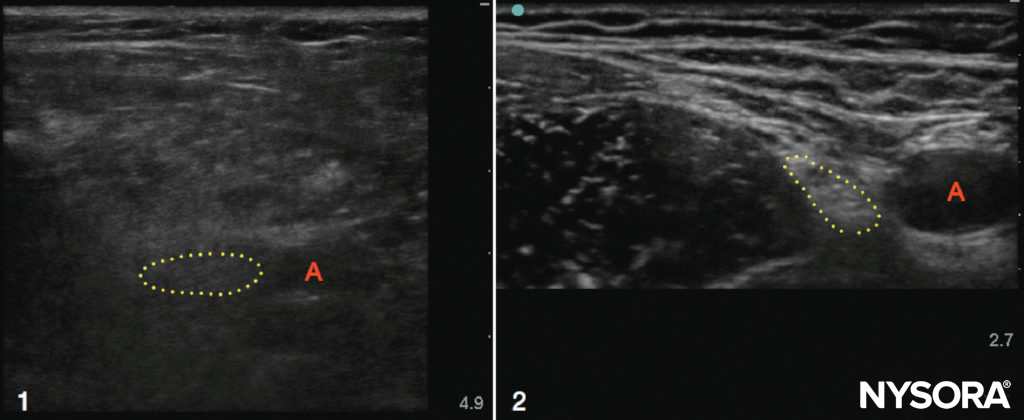

Ultrasound may be especially useful in obese patients with obscured surface landmarks, although excess adipose tissue can make ultrasound examination itself more difficult due to attenuation of the ultrasound beam. This difficulty can be partly overcome by decreasing the frequency of the transducer to increase penetration depth, although image resolution will be reduced (Figure 2). When median and sciatic nerves were scanned in normal-weight and obese volunteers, Marhofer et al. concluded that visualization of superficial peripheral nerves is independent of BMI, whereas deeper nerves are more difficult to visualize in obese subjects. Studies conducted in obese parturients and in nonobstetric patients with difficult surface anatomic landmarks have verified the utility of ultrasound in identifying the epidural space and other spinal structures prior to the performance of a neuraxial block. To date, few studies have compared ultrasound-guided peripheral nerve blocks with landmark or nerve stimulator–guided techniques in the obese population; however, ultrasound seems to be a useful modality for this potentially challenging group of patients.

FIGURE 2. Ultrasound scans of the femoral regions in an obese (1) patient and a slim (2) patient. Note the increased depth required to image the artery (A) and nerve (dotted outline) in the obese example, as well as the overall poor resolution quality due to the excess adipose tissue. In contrast, the nerve, artery, muscles, and fascial planes in the slim patient are crisp and well defined.